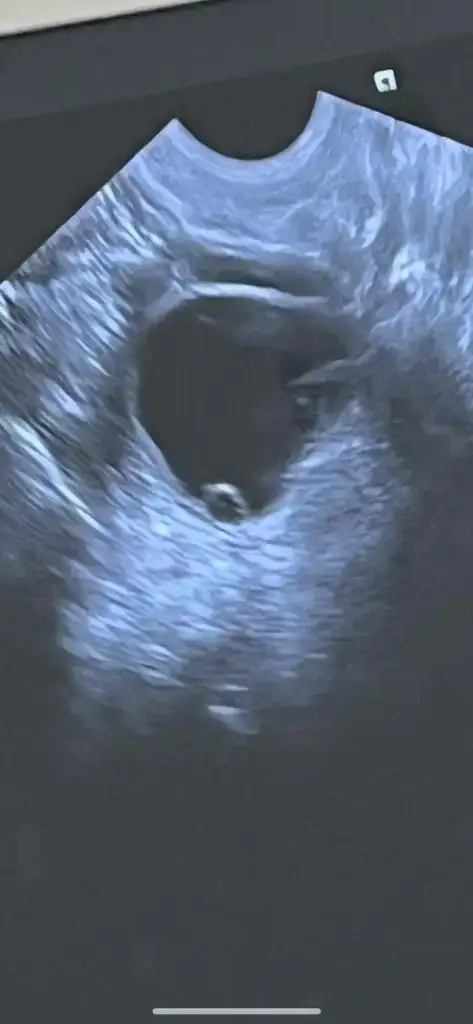

Ultrason görüntüsü de 17 Mart tarihine ait. Yani döngümün 21. günü. Belki USG ultrason görüntüsünden anlayan birileri çıkar :(